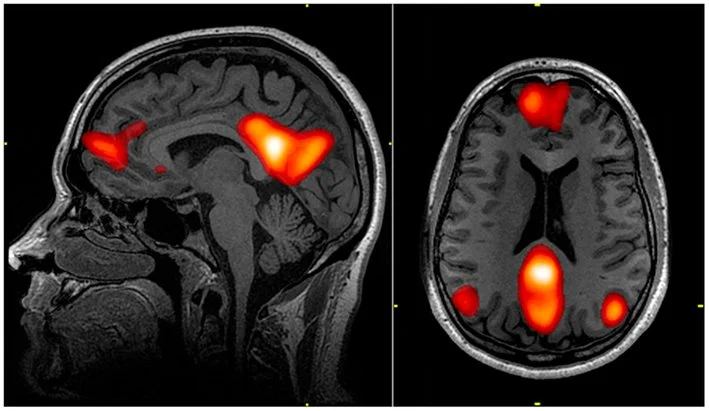

De igual manera considero interesantes el estudio y reinterpretación de imágenes científicas en donde se analizan los efectos neuronales, por ejemplo, en el cerebro de personas que se sienten inmersos en profunda soledad. Creo que la objetividad que da este material, es un aporte interesante que podría nutrir la propuesta, y de una manera más poética refleja mi posición hacia la necesidad de equilibrar nuestra individualidad, (que tiene que ver con el desarrollo tecnológico, rigor científico, la producción y la construcción del yo, etc.), con lo relacional y afectivo (que es la naturaleza y motivación del presente proyecto).

[EN] Likewise, I consider interesting the study and reinterpretation of scientific images where the neuronal effects are analyzed, for example, in the brains of people who feel immersed in deep loneliness. I think that the objectivity that this material provides is an interesting contribution that could nourish the proposal, and in a more poetic way it reflects my position towards the need to balance our individuality, (which has to do with technological development, scientific rigor, production and the construction of the self, etc.), with the relational and affective (which is the nature and motivation of the present project).